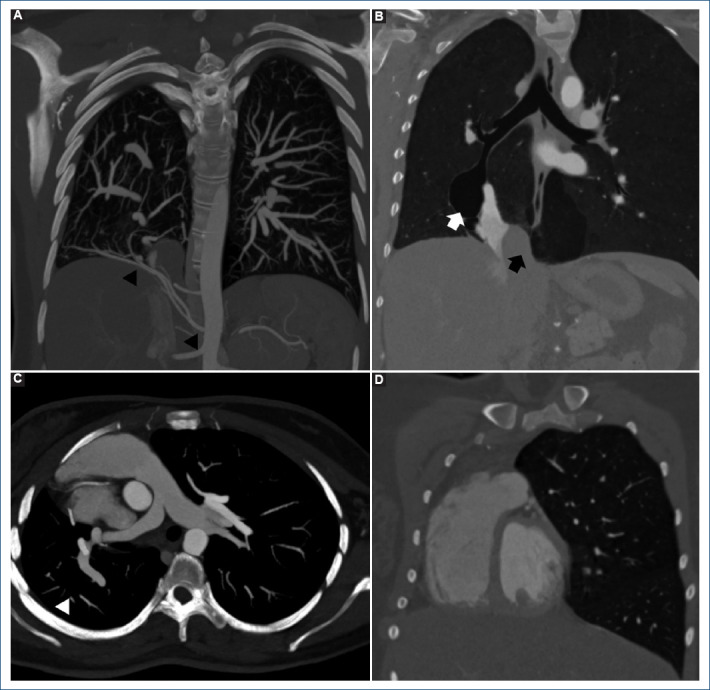

The Ottoman empire sword: a variant of partial anomalous pulmonary veins connections.

{"title":"The Ottoman empire sword: a variant of partial anomalous pulmonary veins connections.","authors":"Karla A Pupiales-Dávila, Vincenzo Arenas-Fabbri, Edgar García-Cruz, Pamela Ramirez-Rangel","doi":"10.24875/ACM.24000029","DOIUrl":null,"url":null,"abstract":"","PeriodicalId":93885,"journal":{"name":"Archivos de cardiologia de Mexico","volume":" ","pages":"122-125"},"PeriodicalIF":0.0000,"publicationDate":"2024-07-29","publicationTypes":"Journal Article","fieldsOfStudy":null,"isOpenAccess":false,"openAccessPdf":"https://www.ncbi.nlm.nih.gov/pmc/articles/PMC12148509/pdf/","citationCount":"0","resultStr":null,"platform":"Semanticscholar","paperid":null,"PeriodicalName":"Archivos de cardiologia de Mexico","FirstCategoryId":"1085","ListUrlMain":"https://doi.org/10.24875/ACM.24000029","RegionNum":0,"RegionCategory":null,"ArticlePicture":[],"TitleCN":null,"AbstractTextCN":null,"PMCID":null,"EPubDate":"","PubModel":"","JCR":"","JCRName":"","Score":null,"Total":0}